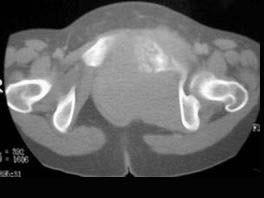

问题 患者,女,54岁,因反复左髋、左下肢疼伴左下肢活动障碍约半年,请结合所提供的图像,选择最佳选项 ( )

选项 A、Ewing肉瘤 B、骨巨细胞瘤 C、滑膜肉瘤 D、骨转移瘤 E、骨髓瘤

答案 A